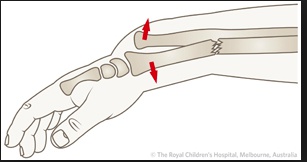

Colles

A dorsally displaced distal radius fracture

.,

Typically the result of a fall on an out-stretched hand (FOOSH) that is in dorsiflexion. Compare this to a Smith’s fracture, which occurs after a fall on an outstretched hand that is in volar flexion.

A Colles’ fracture presents with tenderness and swelling at the distal forearm with or without visible deformity.

Treatment of a Colles’ fracture consists of:

Closed reduction and casting if stable

Closed reduction with percutaneous pinning if unstable

Open reduction with internal fixation if unstable.

Smith

A volar displaced distal radius fracture.

Typically the result of a fall on an out-stretched hand that is in volar flexion., opposite of the dorsiflexion that produces a Colles’ fracture. They are much less common than a Colles’ fracture.

A Smith’s fracture presents with tenderness and swelling at the distal forearm with or without visible deformity, similar to Colles’ fracture.

Treatment of a Smith’s fracture consists of:

Open reduction with internal fixation if unstable